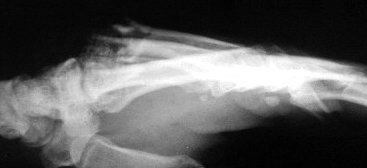

Metacarpal bases protruding through dorsal skin wound.